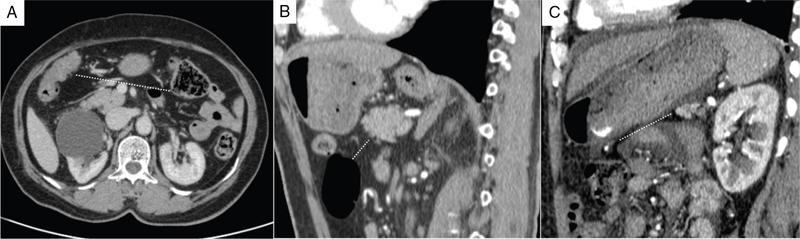

Shivsamb Jalkote, Slesha Bhalja, Disha Lokhandwala, Mansi Jantre, Karthik Ganesan Peritoneum is involved in a diverse group of primary as well as secondary pathologies ranging from the infective/inflammatory spectrum to malignancies. Peritoneal diseases are both common and potentially life threatening, and yet often get neglected in routine evaluation, due to the complex peritoneal anatomy and sometimes subtle imaging manifestations. The radiologist forms an integral part of the multidisciplinary team dealing with peritoneal pathologies and hence, having a lucid understanding of peritoneal anatomy, pathways of disease spread and different treatment options is paramount for an accurate radiological analysis. All three major serosal cavities (pleural, pericardial and peritoneal) of the body are derived from a single coelomic cavity, which is lined by a continuous mesothelium. At 2 weeks of gestational age, during the gastrulation stage, the embryo is a trilaminar disc, composed of the endoderm, mesoderm and ectoderm. During this stage, the development of the coelomic cavity commences as a consequence of morphological changes in the mesodermal cells leading to a coalition of the intercellular spaces. Peritoneum originates from mesoderm with its parietal layer developing from somatic mesoderm and visceral layer developing from splanchnic mesoderm. Initially, the peritoneum is an empty sac into which the growing gut tube protrudes (at 3 weeks of gestational age), resulting in the formation of the dorsal mesentery (formed by the fusion of two layers of the splanchnopleuric mesoderm) by which the gut tube is suspended lengthwise. The mesodermal cells opposed to the gut tube represent the future visceral peritoneum and those lining the body wall and the septum transversum form the future parietal peritoneum. Analogously, the ventral mesentery originates from the mesoderm of the septum transversum with the closure of the anterior abdominal wall, and, is short and not as extensive as the dorsal mesentery. The two mesenteries are aligned in the sagittal plane, subdividing the primitive peritoneum into right and left cavities, which are continuous anteriorly below the inferior edge of the ventral mesentery. With the development of various abdominal organs as buds from the gut tube, the capacity of the abdominal cavity diminishes, pushing the midgut loop into the umbilical cord. This physiologic herniation of the midgut takes place at the 6th week of gestation. Simultaneously, as the peritoneum drapes over the developing organs, there is compartmentalization of the cavity and a pattern of folds develops that eventually form the peritoneal ligaments. The majority of these ligaments arise from the ventral or dorsal mesentery. As the hepatic bud develops within the ventral mesentery, derivatives of the ventral mesentery can be divided based on their relation to the liver. The gastrohepatic ligament (lesser omentum) develops dorsally and the falciform, coronary, and triangular ligaments develop ventral to the liver. Conversely, the dorsal mesentery spans between the gut tube and the posterior abdominal wall, and the spleen and pancreatic tail develop within it. In congruence, it forms the gastrophrenic, gastrosplenic and splenorenal ligaments and peritoneal folds of the small and large intestines. As stated earlier, the dorsal mesentery has a relatively larger caudad extension and since the spleen develops in its upper portion, the rapidly growing mesentery beyond the spleen forms the greater omentum. Finally, the differential growth of the greater curvature of the stomach and the right hepatic lobe results in rotation of the abdominal organs and their mesentery, and the cephalad portion of the peritoneal cavity is divided into a larger ventral cavity, called the greater sac, which caudally communicates with the common peritoneal cavity, and a smaller dorsal cavity called the lesser sac. The key aspects of peritoneal development are summarized in Flowchart 8.6.1 and Fig. 8.6.1. Laparoscopy remains the gold standard in the assessment of peritoneal disease, however, it is an invasive technique, and has certain diagnostic limitations including the inability to assess parenchymal diseases, extraperitoneal diseases, and also has limited utility in the presence of adhesions. Hence laparoscopy is not recommended as the first-line modality and has been replaced by cross-sectional imaging in routine clinical practice. The role of imaging is primarily to assess disease burden in terms of volume and extent and to identify surgically nontreatable disease, which reduces open and shut laparotomies. Peritoneal metastatic disease burden is assessed using peritoneal carcinomatosis index (PCI) both surgically as well as using cross-sectional imaging, details of which will be discussed subsequently. CT, MRI and PET/CT are all commonly used imaging modalities, however, there is no singular universally accepted reference imaging standard for the peritoneal disease. In a recent meta-analysis evaluating the diagnostic performance of imaging in the detection of peritoneal metastasis (PM), authors concluded that MRI (DWI) and PET/CT show comparable diagnostic performance in gastrointestinal and ovarian cancer malignancies however the widespread availability of MRI makes it the more likely imaging modality of choice in the future. The results of this study are summarized in Table 8.6.1. Conventional imaging including radiography and barium studies have a poor diagnostic yield in evaluating peritoneal pathologies. Abdominal radiographs are usually restricted for identifying pneumoperitoneum and bowel obstruction in the setting of acute abdominal pain. Diffuse increase in radio-opacity of the abdomen, poor definition of soft tissue shadows (psoas, liver and spleen), bulging flanks along with medial displacement of small bowel loops from the properitoneal fat stripe are indirect markers of large ascites which can prompt further evaluation with ultrasonography. Indirect features of peritoneal disease on barium studies include mass effect and displacement of adjoining bowel loop, narrowing of bowel loop with bowel dilatation along with nodularity, spiculation, or tethering of adjacent mucosal folds or haustra with sacculation of the uninvolved contralateral border. Barium studies have fallen out of favour in routine radiological practice owing to the widespread use of cross-sectional imaging. Ultrasonography (US) is a readily available and relatively inexpensive imaging tool. Traditionally its role in the evaluation of peritoneal pathologies is limited as US beam gets strongly reflected at the interface of air and visceral structures which leads to obscuration of underlying structures. US remains the primary imaging modality in the evaluation of an acute abdomen and is useful in detecting of ascites, focal lesions and any focal abnormality at the site of tenderness. US has the unparalleled advantage of providing real-time assistance in performing imaging-guided procedures such as paracentesis and peritoneal biopsies. US can be used in characterization of focal lesions (as solid, solid-cystic and cystic) and assessment of internal vascularity using colour Doppler. Transvaginal US provides a good overview of pathologies involving pouch of Douglas besides the uterus and adnexa. Experienced and skilled sonologists can detect omental thickening, peritoneal nodules and small surface deposits using high-frequency transducer (Fig. 8.6.2). Endoscopic US allows assessment of diseases involving peritoneal ligaments besides assistance in a guided biopsy. The reported sensitivity, specificity and accuracy of EUS-FNA versus CT/MRI in detecting PM was 91% versus 28%, 100% versus 85% and 94% versus 47%, respectively. CT is the most commonly employed imaging modality in the evaluation of peritoneal pathologies due to its widespread availability, fast acquisition and high spatial resolution. Current generation multidetector CT scanners (64 slices and above) offer very thin collimation, leading to the acquisition of near isotropic volumetric data which allow reformations in coronal and sagittal images without any added imaging time. It is the modality of choice for preoperative staging in most primary abdominal and pelvic malignancies (e.g. stomach, appendix, ovary) owing to its ability to detect local and regional infiltration, nodal involvement and distant metastases. CT is also used to evaluate PCI and detect disease in critical and occult locations, thus significantly altering further management strategies. CT is the most common imaging modality used in postoperative surveillance and evaluation of postoperative recurrence. CT protocol includes administration of both enteric contrasts (oral and rectal) and intravenous contrast (Table 8.6.2). Optimal bowel distension is key as collapsed loops can mimic disease and also mask the serosal and endoluminal disease. Often, a CT scan of the chest is performed as an adjunct to rule out pleuroperitoneal/transdiaphragmatic dissemination. Helical (≥64 slice scanner) Dual energy scanner if available As thin as possible (≤1 mm) Same as section thickness without gap From xiphisternum to pubic symphysis Chest included if suspicion of thoracic involvement 1 L of positive oral contrast over duration of 60 minutes and 500 mL of positive rectal contrast on table before administration of IV contrast 1.5–2 mL/kg of nonionic contrast with high iodine concentration (≥ 300) at rate of 3–5 mL/sec Unenhanced imaging not recommended. Monophasic acquisition at 60 seconds usually sufficient in majority cases Arterial phase at 20 seconds acquired for arterial assessment Delayed phase in cases of ureteric obstruction, slow bowel transit and suspected leak. Axial 1 mm thickness, multiplanar reformats in coronal and sagittal planes at 1 mm MIP or 3D volumetric sections for vascular assessment There is a wide range of reported diagnostic accuracy (sensitivity ranging from 25% to 100%, specificity ranging from 78% to 100%) of CT in the assessment of PM depending on the expertise of the reader and scanner type. In general, key factors affecting CT sensitivity include the size of lesion, the region of affection and presence of ascites. 64 slice scanners with multiplanar reformations allow 100% sensitivity and positive predictive value in detecting lesions measuring >5 cm, which partly diminishes for lesions between 0.5 cm and 5 cm in size with sensitivity and positive predictive being 83% and 93%, respectively. It receives the most criticism in the evaluation of lesions < 0.5 cm with significantly low sensitivity and positive predictive value (43% and 76%, respectively). There is also a great degree of variation in sensitivity based on the anatomical location of the disease. In a study by Koh et al., the detection rates ranged from 8% to 67%, depending on the region involved; only the epigastrium exceeded 60%, with the small-bowel disease being the most poorly visualized (8%–14%). The sensitivity for tumour detection in epigastrium, greater omentum and under surfaces of the diaphragms was 60%–90%, while it was 50%–70% in the retroperitoneum and pelvis, and small bowel-mesentery involvement was detected in merely 20%–50% of cases. These are noteworthy findings, as small-bowel involvement has major implications on outcome and is one of the limiting factors for complete cytoreduction. Poor soft tissue resolution of CT doesn’t allow accurate differentiation between mucinous deposits from ascites. Administration of positive enteric contrast can mask calcified serosal deposits. DECT uses two separate x-ray energy spectra and allows characterization of tissues based on their differences in attenuation properties at different energies. Though the role of DECT in the assessment of abdominal pathologies is increasingly reported in the literature, there are very limited data available on its application in assessment of peritoneal pathologies. The combination of iodine overlay with conventional imaging has shown a better specificity in differentiating PM from benign peritoneal entities, and hence can be particularly useful in the postoperative setting. MR imaging offers excellent soft tissue resolution, multiplanar capabilities and avoids exposure to ionizing radiation, making it an attractive tool for evaluation of peritoneal diseases. MRI is better suited and can be problem solving in visualization of smaller lesions (<1 cm) and assessment of relatively concealed areas such as subphrenic, mesenteric and bowel serosa. Unenhanced T1- and T2-weighted images can show larger peritoneal deposits and masses but are relatively insensitive for the depiction of smaller lesions. The combination of diffusion-weighted imaging (DWI) and delayed gadolinium-enhanced MR imaging is considered the most accurate technique for detecting peritoneal tumours (Fig. 8.6.3). MRI protocol for assessment of peritoneum has been detailed in Table 8.6.3. In a study by Low RN et al., MRI PCI correctly categorized tumour volume in 91% of patients compared to surgical PCI, as opposed to 50% with CT. In addition, MRI demonstrated per site sensitivity of 95%, specificity of 70% and accuracy of 88%, while CT showed a corresponding per site sensitivity of 55%, specificity of 86% and accuracy of 63%. MRI PCI has also shown to have better prediction of intraoperative burden of disease for invasive appendiceal and peritoneal mesothelioma histologies as compared to CT-PCI. *This general imaging protocol is based on 3 T MRI Siemens system, covers both abdomen and pelvis. Protocol is modified depending on primary disease and type of scanner. Low RN. Preoperative and surveillance MR imaging of patients undergoing cytoreductive surgery and heated intraperitoneal chemotherapy. Journal of gastrointestinal oncology. 2016 Feb;7(1):58. The higher cellularity of majority of peritoneal nodules results in restriction of water movement and corresponding high signal intensity on DW images. On the higher b-value images, bowel contents are suppressed and the serosal and peritoneal tumours become hyperintense. DWI is also useful to demonstrate associated lymphadenopathy, hepatic and osseous metastases. In a study by Zhang et al., in PC of colorectal carcinoma, DWI demonstrated sensitivity of 69.4%, 91.3% and 100% for lesions measuring <0.5 cm, 0.5–5.0 cm and >5 cm, respectively. The overall sensitivity, specificity and accuracy of DWI for the detection of peritoneal tumours were 80.3%, 84.5% and 82.1%, respectively. DWI/MRI is also superior in demonstrating lesions involving small bowel wall, with an accuracy of 92%–95% versus 48% for CT. Reported negative predictive value of DWI for small bowel serosal metastases is 100%. Whole-body DWI/MRI was highly accurate for the prediction of inoperability (PPV 100%, NPV 90.3%) and was capable of detecting metastases both inside and outside the abdominal cavity. Peritoneal tumours enhance slowly and are best depicted on the final set of images obtained about 5 minutes following gadolinium administration. The increased conspicuity of these enhancing peritoneal tumours improved detection of small tumours that are often missed on CT scans. For this reason, perfect breathhold is essential while obtaining the final set of images and if images are acquired later, contrast that has diffused into the ascitic fluid can obscure smaller lesions. The high-contrast conspicuity of fat-suppressed and delayed gadolinium-enhanced MRI makes it the imaging modality of choice in depicting subcentimetre deposits (including those measuring <5 mm), and also deposits in anatomically concealed sites (e.g., subphrenic, mesenteric and bowel serosa). Gadolinium-enhanced MRI has higher sensitivity in detecting peritoneal lesions <1 cm which is about 85%–90% compared to 22%–33% for CT. Despite the clear superiority of MRI over CT, the major detractors against MRI are the long exam times and the higher expense burden. Longer acquisition times can lead to motion artefacts related to respiration and bowel peristalsis compromising detection of smaller lesions. MRI is contraindicated in patients with pacemakers, cochlear implants and claustrophobic patients with some exceptions. DW-MRI is less sensitive in special histological subtypes such as signet ring cell and mucinous adenocarcinoma due to their limited restricted diffusion. The combined use of FDG-PET with anatomical CT imaging, provides the added benefit of qualitative and semiquantitative metabolic analysis (Fig. 8.6.4). PET/CT has an established role in staging of most of the primary tumours of the chest, abdomen and pelvis. It is also helpful in assessing malignant ascites or PM of an unknown primary. In disseminated malignancies, it can localize the optimal site for biopsy depending upon metabolic activity of the lesion. PET/CT should be used selectively in preoperative assessment of patients with large tumour volumes and poor prognostic histologies being considered for CRS and HIPEC to rule out extra abdominal metastases. It can also detect extraabdominal metastases, including mediastinal and supraclavicular nodes, and other organ sites, such as bone and brain. It can also detect nodal involvement in normal-sized lymph nodes seen on conventional cross-sectional imaging. PET/CT also plays a role in disease surveillance and assessment of response to neoadjuvant chemotherapy. This is particularly relevant in malignancies where anatomical changes are so small that measurement of size change alone becomes unreliable and also in differentiating between residual/recurrent disease and postoperative changes after CRS and HIPEC. Besides oncological indications, PET/CT is also helpful in assessment of benign and inflammatory diseases to evaluate disease extent and also localize the site for biopsy. In cases of pyrexia of unknown origin, PET/CT has often been employed to demonstrate unsuspected peritoneal disease. Utility of PET/CT in peritoneal disease assessment is limited in developing counties due to its higher cost burden and lower accessibility. Certain histological subtypes such as mucinous and signet ring cell carcinomas show low FDG uptake making PET/CT less sensitive. Low metabolic uptake in these subtypes is thought to be due to low tumour cell density, higher content of metabolically inert mucin and lack of expression of glucose transporter Glut-1. This is more relevant in context of colorectal malignancy where mucinous carcinoma and signet ring cell carcinoma more frequently metastasize to the peritoneum compared to adenocarcinoma (48%, 51% and 20%, respectively). PET/CT is prone to artefacts caused by misregistration between the CT and PET images which can lead to inaccurate assessment of certain regions such as dome of diaphragm and structures adjoining the urinary bladder, making the detection of pelvic implants difficult due to partial volume effects. Implants against the small bowel and mesentery may be obscured by the physiological metabolic activity of bowel. Pretreatment PET/CT demonstrates a higher accuracy than CT for nodal and metastasis staging but has limited sensitivity to detect PM, especially when there is small-volume disease as only 13.6% of the nodules less than 0.5 cm were correctly identified by PET/CT. Table 8.6.4 summarizes role of different imaging modalities for assessment of peritoneal diseases. Peritoneum is the largest serosal membrane in human body with surface area of about 2.2 m2. It is composed of parietal and visceral layers which are continuous with each other, with parietal peritoneum lining the coelomic cavity and visceral peritoneum lining the visceral organ (Fig. 8.6.5). The peritoneum essentially minimizes friction, resists infection and stores fat, allows free movement of the abdominal viscera which gets restricted in presence of adhesions. Peritoneum acts as first line of defence in controlling disease spread, and, it exudes fluid and cells in response to injury or infection (peritonitis), to wall off or localize infection. In natural states, intraperitoneal spread of infection is limited by lymphoid aggregates and stomata on both the peritoneal layers. Omentum is commonly known as policeman of abdomen as it migrates to the site of infection and isolates affected area from healthy tissues. Iatrogenic violation of peritoneum following surgery can lead to recurrence along the operative incision scar sites and along the vaginal cuff following hysterectomy in pelvic malignancies. The parietal peritoneum is supplied by nerves (e.g. phrenic and thoracoabdominal) to the adjacent body wall, and is predominantly very sensitive to pain, which explains the typical referred shoulder pain from upper abdominal pathologies such as gall stones and pancreatitis. The visceral peritoneum is insensitive to pain and responds mainly to stretching. These two layers encompass a potential space, called the peritoneal cavity which contains approximately 50–75 mL of clear serous fluid. Peritoneal cavity is a closed space in males while in females it communicates with extraperitoneal pelvis through ostia of fallopian tubes allowing transport of ovum. This communication serves as natural route for ascending spread of sexual transmitted disease from genital organs into peritoneal cavity leading to pelvic inflammatory disease and uncommonly perihepatitis (Fitz–Hugh–Curtis syndrome). The invaginations of the peritoneum result into formation of three different types of structures namely ligaments, omentum and mesentery (Figs. 8.6.6–8.6.9) which serve as bridges that permit blood, lymph vessels and nerves to reach the viscera. Ligaments are double folds of peritoneum that connect one organ to another organ or to the abdominal wall and are named usually after the respective viscera. The liver, for example, is connected to the diaphragm by the falciform ligament, coronary ligament and right and left triangular ligaments. Mesenteries are double folds of peritoneum that suspend intestine to the posterior abdominal wall (retroperitoneum) such as the small bowel mesentery, transverse and sigmoid mesocolon. Omentum are double folds of peritoneum that extends from the stomach to other organs and include the greater and lesser omentum. Table 8.6.5 summarizes the peritoneal ligaments in abdomen and pelvis. In medical school days, the anatomy textbooks traditionally divided abdomen and pelvis into tricompartmental model comprising of peritoneal cavity, retroperitoneum and extraperitoneal spaces. This model is good for basic understanding of anatomy and confinement of certain disease processes but fails to explain spread of diseases from retroperitoneum to peritoneum besides spread of some disease processes within peritoneal cavity itself. Considering these shortcomings of conventional description of anatomy, the unifying concept of subperitoneal space has evolved in literature and is getting accepted increasingly. As per this concept, abdomen and pelvis are divided in two spaces peritoneal cavity and subperitoneal space which are separated from each other by peritoneum. Subperitoneal space (Fig. 8.6.10) is large anatomically continuous potential space which connects peritoneal cavity with retroperitoneum. It constitutes the subserosal areolar tissue and fat tissue lining the inner surfaces of the peritoneum and the abdominopelvic musculature. The omentum, ligament and mesentery are the interconnecting peritoneal folds building the subperitoneal space. All the abdominal and pelvic organs along with their vascular, lymphatic and nervous supplies are situated within subperitoneal space. With this concept, we want to correct the common misconception of intraperitoneal organs as in strict terminology there is no organ within the peritoneal cavity itself. It is imperial to understand differences between peritoneal and subperitoneal spaces as these are mutually exclusive spaces having distinct patterns of disease spread which we will discuss in subsequent sections. In resting state, peritoneal cavity is collapsed and thus not visible on routine imaging. Peritoneal cavity usually gets distended due to disease processes composed of fluid, air or masses. The peritoneal cavity is divided into two parts: the greater sac and the lesser sac which communicate with each other via an epiploic foramen (of Winslow). The greater sac forms main peritoneal cavity and extends from the diaphragm down into the pelvis. The lesser sac is small diverticulum and lies between stomach and pancreas. For better understanding, abdominal peritoneal cavity is divided into supra- and inframesocolic compartments, communicating with pelvic peritoneal cavity which is further divided by other peritoneal folds and reflection (Flowchart 8.6.2, Figs. 8.6.10 and 8.6.11). Supramesocolic compartment (Fig. 8.6.12) is situated between the diaphragm and transverse mesocolon. It is arbitrarily divided into right and left supramesocolic peritoneal spaces, which can be further subdivided into a number of subspaces by upper abdominal organs and peritoneal ligaments. Right supramesocolic space is divided into three subspaces: right subphrenic space, right subhepatic space and lesser sac. Right subphrenic space is partially separated from right subhepatic space by right triangular ligament. Right subphrenic space is situated between right hemidiaphragm and right lobe of liver (superior, anterior and right lateral surfaces). It is limited posteriorly by the coronary ligament and medially by the falciform ligament with the latter separating it from the left subphrenic space. Right subhepatic space is situated inferior to right lobe of liver and has anterior and posterior components. Anterior component is limited inferiorly by transverse mesocolon whereas the posterior component extends anterior to right anterior perirenal fascia. Posterior component of right subhepatic space is commonly known as hepatorenal pouch (of Morrison) and forms most dependent site in supine position, thus being a common site of fluid accumulation. The right subhepatic space freely communicates with right subphrenic space superiorly and right paracolic gutter inferiorly. Lesser sac (also known as omental bursa) is situated superior to the transverse mesocolon, anterior to pancreas and posterior to the lesser omentum, stomach and gastrocolic ligament. Lesser sac (Fig. 8.6.13) communicates with right subhepatic space (of greater sac) via epiploic foramen which is bounded by IVC posteriorly, free margin of hepatoduodenal ligament anteriorly, D1 (first part of duodenum) caudally and caudate lobe of liver rostrally. Division of lesser sac into smaller superior compartment (superior recess) and larger inferior compartment (inferior recess and splenic recess) is accomplished by prominent crescentic gastropancreatic fold (peritoneal fold overlying common hepatic and left gastric artery) which extends from neck of the pancreas to the upper part of lesser curvature of stomach. The superior recess is situated to the right of midline above pancreas and posterior to lesser omentum. It surrounds the medial aspect of the caudate lobe and superiorly into the fissure for the ligamentum venosum. Splenic recess extends to splenic hilum, and is limited by gastrohepatic ligament (anterior), gastrosplenic ligament (lateral) and splenopancreatic ligament (posterior). Inferior recess is located to left of midline, separates stomach from the pancreas and transverse mesocolon. In few cases, an infrapancreatic part can be seen due to persistence of inferior recess within the greater omentum or due to downward bowing of transverse mesocolon. Left supramesocolic space is wider than right supramesocolic space and is limited above by left hemidiaphragm and below by transverse mesocolon and phrenicocolic ligament. Left supramesocolic space (subphrenic part) is medially separated from right supramesocolic space by falciform ligament and inferiorly from left paracolic gutter by phrenicocolic ligament. It is divided into four communicating subspaces: anterior left subphrenic space, posterior left subphrenic space, anterior left perihepatic space and posterior left perihepatic space. All these spaces communicate with each other. The definitions of the boundaries of these spaces vary in literature. Anterior left subphrenic space is situated between gastric fundus and left hemidiaphragm. Posterior left subphrenic space (also known as perisplenic space) surrounds spleen. Anterior left perihepatic space is situated between anterosuperior aspect of left lobe of liver and left hemidiaphragm. Posterior left perihepatic space (also known as gastrohepatic recess) is situated between inferior aspect of left lobe of liver and lesser omentum. Inframesocolic compartment (Fig. 8.6.14) extends below transverse mesocolon to the level of pelvic brim and is divided into large central part and smaller paracolic part (lateral recesses). Central portion of inframesocolic compartment is unequally divided by obliquely oriented small bowel mesentery leading to formation of smaller right inframesocolic compartment and larger left inframesocolic compartment. Right inframesocolic space terminates at the ileocaecal junction and does not communicate with pelvis. Left inframesocolic space is in communication with pelvic peritoneal spaces except at the sigmoid mesocolon attachment which offers partial barrier. Peritoneal recesses on the posterior abdominal wall lateral to the ascending and descending colon form right and left paracolic gutters respectively. Both paracolic gutters communicate freely with pelvic peritoneal spaces. Right paracolic gutter is deeper than left gutter and is in free communication with right supramesocolic space. Left paracolic gutter is partially limited from left supramesocolic space due to presence phrenicocolic ligament. Pelvis constitutes about one-third of the total volume of the peritoneal cavity and is most dependent part in both supine and erect positions. Inferiorly peritoneum drapes over fundus of urinary bladder, anterior and posterior surface of uterus and upper posterior vagina in females and anterolateral surface of the upper rectum leading to formation of different peritoneal spaces. The urinary bladder subdivides pelvis into anterior and posterior paravesical spaces. The anterior paravesical space is further compartmentalized by remnant of the urachus (median umbilical ligament), the obliterated umbilical arteries (medial umbilical ligament), and the lateral umbilical ligaments (inferior epigastric vessels) into five fossae: the right and left lateral and medial inguinal fossae and the supravesical fossa. The supravesical space is seen in midline with medial and lateral inguinal fossae placed on either side. The supravesical space lies above urinary bladder between the two medial umbilical folds, is usually occupied by small bowel loops and fundus of distended urinary bladder. Just lateral to the supravesical space is the medial inguinal fossa, located between the medial and lateral umbilical folds. The femoral ring is located inferolaterally and hence ascitic fluid in the medial inguinal fossa can extend into the femoral canal. Finally, the lateral inguinal fossa is located between the lateral umbilical fold and parietal peritoneum (which reflects over the vas deferens or round ligament). It usually contains the cecum or ileum on the right and sigmoid colon on the left. Extension of ascitic fluid into the inguinal canal can occur through the deep inguinal ring, located anteromedial to the lateral inguinal fossa. The posterior paravesical space is a larger recess situated between the urinary bladder and rectum. In women, uterus further divides it into smaller vesicouterine and larger rectouterine spaces. The vesicouterine space is located between the urinary bladder and uterus and is formed as the peritoneum drapes the uterine body and fundus and then runs over the urinary bladder (along its posterosuperior surface). It is continuous with the supravesical space anteriorly and its depth varies with the degree of urinary bladder distension. The rectouterine pouch (of Douglas) is delimited anteriorly by the uterus and broad ligaments and posteriorly by the rectum. Lateral to this cul-de-sac on either side are the uterosacral ligaments that run from the sacrum to the uterine cervix that separate the rectouterine pouch from the laterally located ovarian fossae. In men, the rectovesical pouch is formed as the peritoneum runs from the rectum to the posterior surface of the bladder. Posteriorly, the peritoneal reflection from the upper rectum runs to the pelvic sidewalls, forming right and left pararectal fossae, which vary in size with the degree of rectal distension. Analogous to the uterosacral ligaments in women, the rectovesical space is restricted by sacrogenital folds on either side, which extend from the urinary bladder to the sacrum. The rectovesical space and rectouterine space (pouch of Douglas) form most dependent areas in both in supine and standing positions in males and females, respectively (both in supine and standing positions). The key aspects of pelvic peritoneal spaces are summarized in Flowchart 8.6.3, Figs. 8.6.15 and 8.6.16. Peritoneal recesses represent small pockets or fossae in the peritoneal cavity bounded by folds of peritoneum and possibly represent developmental aberrations. Knowledge of these recesses is important as they can serve as pathways for internal hernias. Multiple peritoneal folds may surround fourth part of duodenum (D4) and duodenojejunal junction forming duodenal recess. Six major duodenal recesses include superior, inferior, paraduodenal, retroduodenal, duodenojejunal and mesentericoparietal recess. The superior duodenal recess is situated to the upper left side of fourth part of duodenum (D4) behind the superior duodenal fold at L2 level. Inferior mesenteric vein is situated behind lateral end of superior duodenal fold. Inferior duodenal recess is situated on left of D4 below DJ flexure and behind the inferior duodenal fold at L3 level. Inferior duodenal recess often exists in association with superior duodenal recess. Reported incidence of superior and inferior duodenal recesses is about 40%–50% and 70%–75%, respectively. Paraduodenal recess is seen on left side and slightly behind D4 bounded anteriorly by paraduodenal (falciform fold). Right free margin of paraduodenal fold contains the inferior mesenteric vein and an ascending branch of the left colic artery. This recess is seen in about 2%–3.8% cases and is site for left paraduodenal hernia. Retroduodenal recess as the name suggests situated behind the third and fourth parts of the duodenum and in front of abdominal aorta. Its orifice is bounded anteriorly by duodenoparietal fold. Retroduodenal space is largest among all the duodenal recesses and is seen in about 2.5% cases. Duodenojejunal recess is situated between the duodenojejunal flexure and root of transverse mesocolon, hence also known as mesocolic recess. Its boundaries include pancreas (superior), left renal vein (inferior) and left kidney (left). Its opening lies between two peritoneal folds, is directed inferiorly and to the right. Duodenojejunal recess is seen in about 20% cases and is almost never associated with other duodenal recesses. Mesentericoparietal recess is situated below third part of duodenum and behind the upper part of the mesentery. Its opening is bounded anteriorly by the fold of mesentery raised by the superior mesenteric artery. This recess is most rare among all with incidence of about 1%. It is the site for right paraduodenal hernia. The key aspects of duodenal recesses are summarized in Table 8.6.6 and Fig. 8.6.17. Peritoneal folds adjoining cecum result in formation of four main recesses: superior ileocaecal recess, inferior ileocaecal recess, retrocaecal recess and paracolic recess (Fig. 8.6.18). Surgically these recesses are important as they can be sites for internal herniation (except for paracolic sulci) or site of abscess formation in complicated appendicitis. Superior ileocaecal recess is bounded in front by the vascular fold of the cecum (containing anterior caecal vessels), behind by the ileal mesentery, below by the terminal ileum and on the right by the ileocaecal junction with its opening on left. Inferior ileocaecal recess is bounded in front by the ileocaecal fold (bloodless fold of Treves), above by the terminal ileum and its mesentery, to the right by the caecum, and behind by the upper part of the mesoappendix with its opening on left. Retrocaecal recess is bounded in front by posterior wall of cecum (and sometimes the proximal ascending colon), behind by the parietal peritoneum (posterior abdominal wall), and on either side by two caecal folds (parietocolic folds). Retrocaecal recess is largest among all the caecal recesses with its opening inferiorly and often contains appendix. Paracolic sulci represent variable one or more shallow lateral depressions in the peritoneum investing the cecum usually within the right paracolic gutter. This recess lies behind and inferior to the apex of inverted V-shaped root of sigmoid mesocolon with orifice opening inferiorly. Posteriorly, it is limited by parietal peritoneum of covering the left ureter at its iliac vessel crossing. This recess can be variable in size ranging from dimple to a small fossa in majority of the cases usually admitting little finger. It forms most common site of sigmoid mesocolon hernia. It can also be involved by peritoneal fluid and metastatic disease. Peritoneal and subperitoneal spaces are mutually exclusive spaces having distinct patterns of disease spread. Different pathways of the intraabdominal and extraabdominal disease spread are summarized in Table 8.6.7.

Subperitoneal space